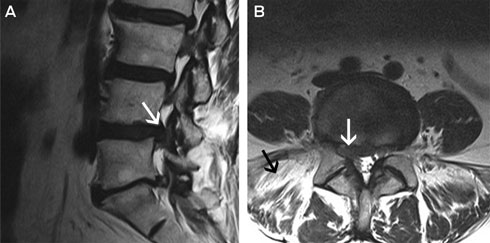

Hilary’s symptoms did not resolve with conservative management and she was referred to a neurosurgeon. MRI of her lumbar spine was performed, which showed broad-based posterolateral L4/L5 disc herniation with compression of the right L5 nerve root (Box 5). The scan also showed fatty replacement of the right paraspinal muscles, suggesting denervation atrophy and indicating chronicity. This also excluded a plexopathy (Box 5) and indicated that no further investigation was necessary.

It is important to attempt to localise the neuroanatomical cause of the clinical signs, as multilevel disc herniations are common in older adults and it can be unclear radiologically which level is primarily responsible for a patient’s symptoms. Clinical and radiological correlation can confirm an L4/L5 disc protrusion — most commonly in the posterolateral direction, which can compress the L5 nerve root in the lateral recess of the spinal canal (Box 3), and less commonly in the far lateral direction, which can compress the descending L4 nerve root.